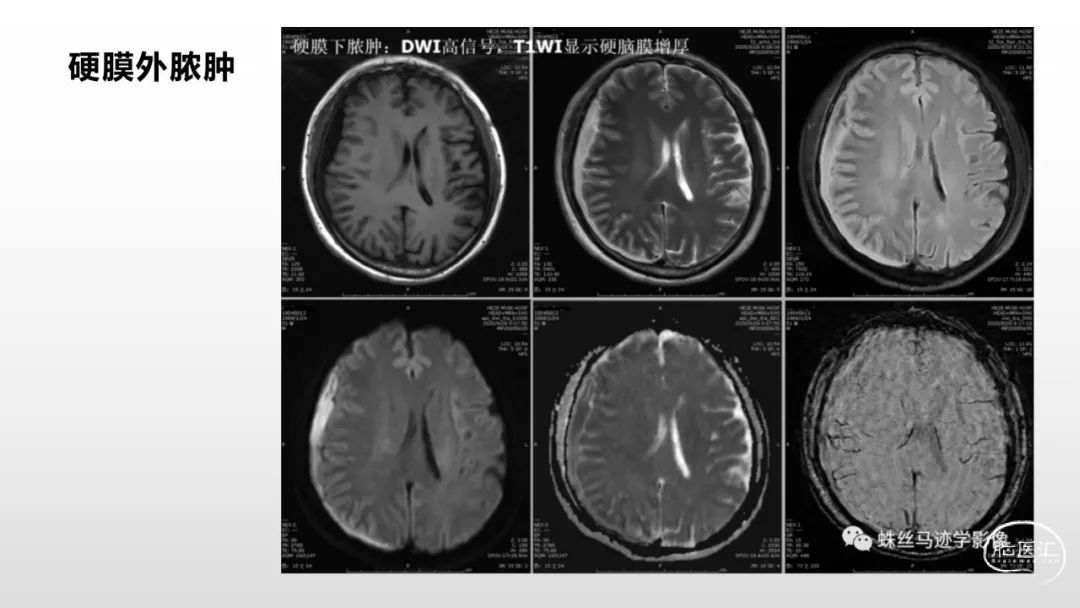

颅脑影像诊断基础知识讲座:脑膜病变